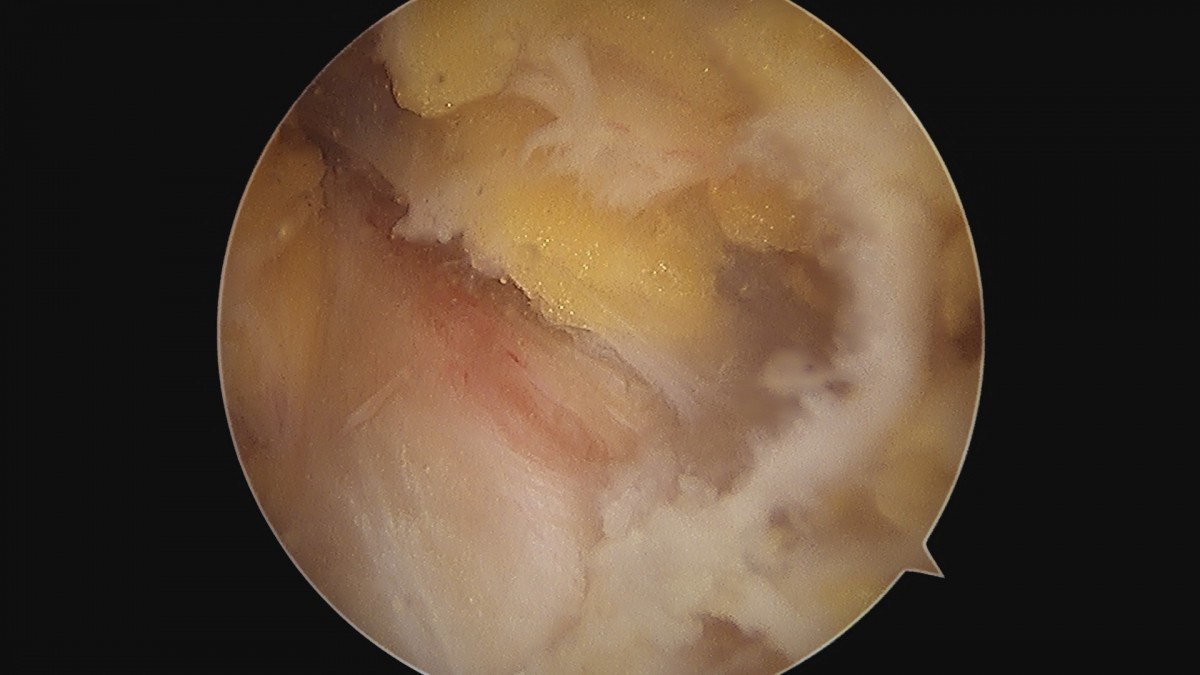

이재상원장님 무릎 반월상 연골판 절제술 안경O 환자

dae765e4d9ac96aee867c9d6292d8784_1758005874_6237.jpg